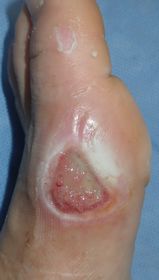

7歳男。

2015年10月26日夕方,自転車に乗っていて車と接触し転倒。左足内側に怪我。直ちに当院ERを受診し,プラスモイストで治療。

翌日,当科を受診。左第1趾MTP関節部に直径2センチ大の全層皮膚欠損あり。プラスモイストで被覆。

| 10月27日 | 10月29日 | 11月6日:10日後 | 11月13日:17日後 |